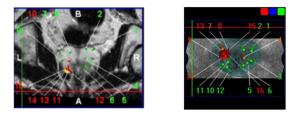

En pratique, lors d’une intervention, le patient est allongé sur le côté gauche. Un appareil spécial combine des images d’échographie 3D et d’IRM (imagerie par résonance magnétique). Grâce à ces images, on peut tracer précisément les contours de la prostate. Ensuite, la cible à prélever (visible sous forme d’une boule jaune sur l’IRM) est identifiée. On refait alors la même démarche avec l’échographie pour bien repérer la prostate. Une fois que les deux images sont superposées, cela permet de guider le prélèvement des biopsies exactement dans la zone ciblée (la boule jaune). La précision de ce dispositif est de quelques millimètres.

À la fin, les résultats des prélèvements apparaissent : les zones où des cellules cancéreuses sont présentes sont en rouge, et les carottes négatives sont en vert. Ces informations sont sauvegardées et pourront servir pour d’autres traitements (comme les ultrasons focalisés, la curiethérapie) ou pour le suivi du patient. Cette méthode permet aussi de comparer des biopsies prises à différents moments. On obtient un compte-rendu avec les mêmes informations codifiées pour tous les spécialistes.